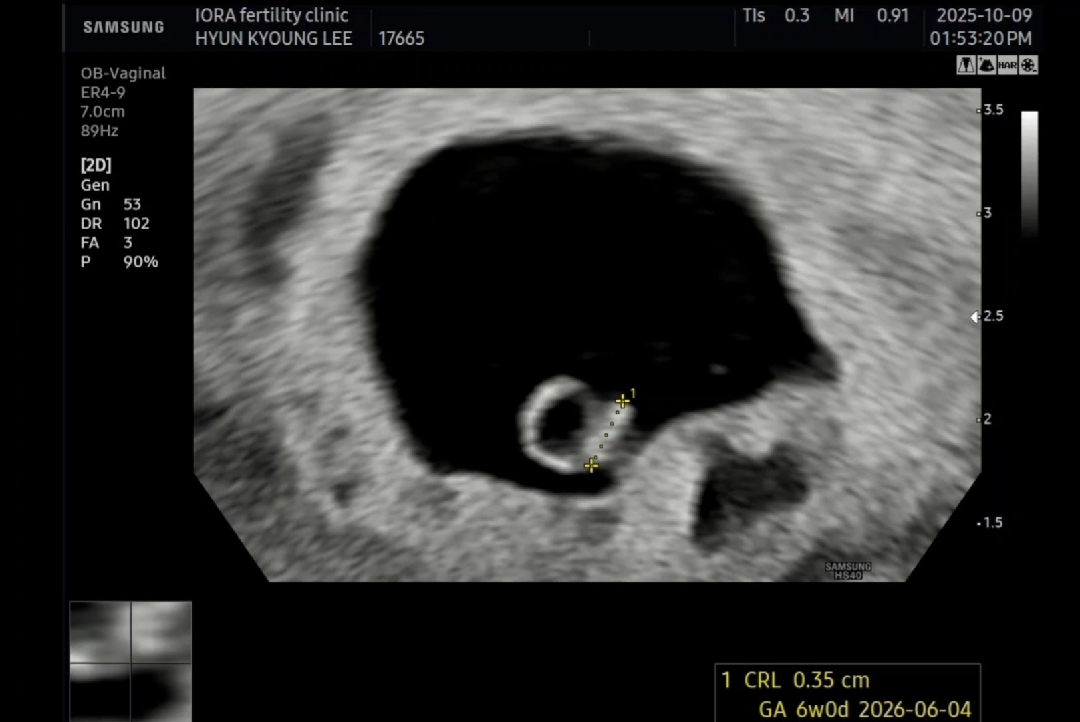

저도 오늘 초음파보고 심소듣고 왔는데 아기 0.3cm로 주수맞게 잘크고있다고 했어요ㅎㅎ 6주2일입니다~

초음파봐주세요~(6주+1)

오늘 심장소리 듣고왔어요>.< 근데 피고임 있다고... 오른쪽아래... 제눈에는 넘 커보이는데 병원에선 아직 아기집 만드는 시기라 그럴수 있다곤 했지만 걱정이 걱정이ㅠㅠ 보통 피고임 생기면 저정도 크기인가요? 아가크기 아직 3.5mm 너무 작아요... 6주에 강낭콩크기라는데 작은거 아닌가 걱정도 되구요...